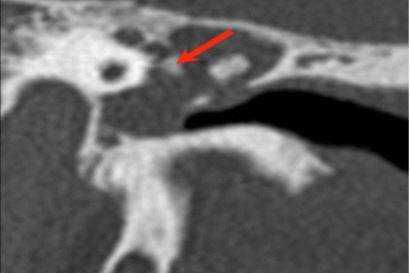

Хроническое воспаление среднего уха: осевая КТ демонстрирует очаговую кальцификацию (стрелка) в барабанной полости - тимпаносклероз.